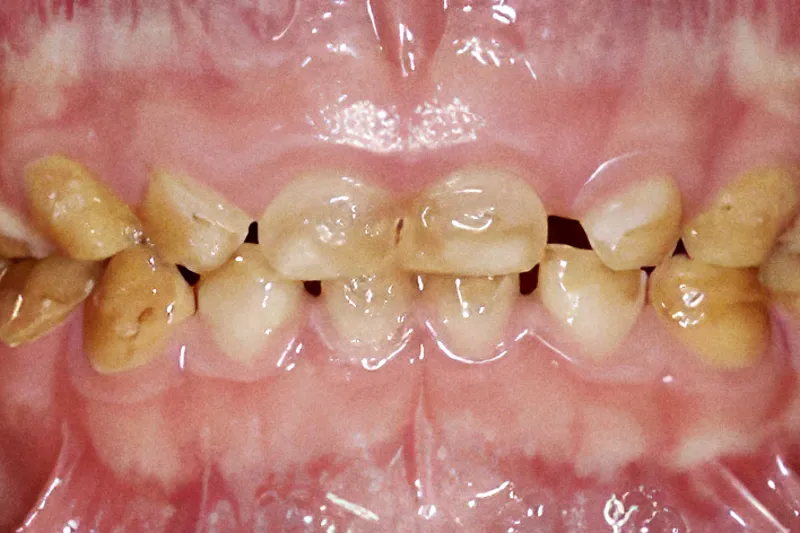

Denne artikel omhandler genetisk betingede misdannelser af emalje eller dentin, hhv. amelogenesis imperfecta og dentinogenesis imperfecta.

Denne artikel omhandler genetisk betingede misdannelser af emalje eller dentin, hhv. amelogenesis imperfecta og dentinogenesis imperfecta. Ætiologi og diagnose af typiske tandforandringer, som ses ved sygdommene, gennemgås. Artiklen omhandler desuden beskrivelse af relevante dele af sundhedsloven, henvisningspraksis med relevans for området samt aktuelle anbefalinger for så vidt angår den forebyggende og rekonstruktive tandbehandling hos børn og unge med disse tilstande.

De hyppigst forekommende genetisk betingede afvigelser i tanddannelsen er amelogenesis imperfecta og dentinogenesis imperfecta, hvor dannelsen af henholdsvis emalje og dentin er blevet forstyrret. For afvigelser gælder, at både den primære og permanente dentition er afficeret, men med stor variation i fænotyper og behandlingsbehov. Det er bl.a. klinisk udfordrende, at kvaliteten af vævene kan være forringet, hvorved en basal egenskab som fx bindingsstyrken mellem tand og en restaurering også er nedsat. Dette betyder nedsat holdbarhed og højere omlavningsrate hos disse patienter og risiko for højere cariesprævalens. Det er derfor nødvendigt med særlig profylaktisk opmærksomhed. Det er vigtigt at kende til de forskellige typer af afvigelser for at kunne iværksætte optimal forebyggelse og relevant tandbehandling og vurdere, om henvisning til specialiseret oral rehabiliterende behandling er nødvendig.